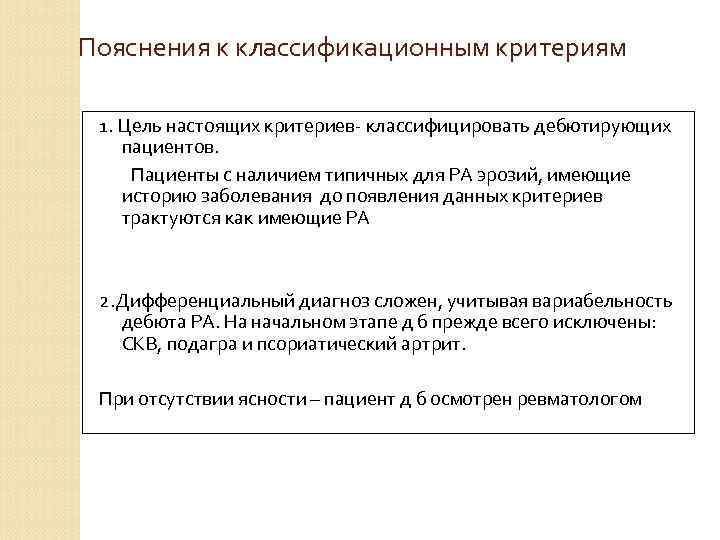

Пояснения к классификационным критериям 1. Цель настоящих критериев- классифицировать дебютирующих пациентов. Пациенты с наличием типичных для РА эрозий, имеющие историю заболевания до появления данных критериев трактуются как имеющие РА 2. Дифференциальный диагноз сложен, учитывая вариабельность дебюта РА. На начальном этапе д б прежде всего исключены: СКВ, подагра и псориатический артрит. При отсутствии ясности – пациент д б осмотрен ревматологом

Пояснения к классификационным критериям 1. Цель настоящих критериев- классифицировать дебютирующих пациентов. Пациенты с наличием типичных для РА эрозий, имеющие историю заболевания до появления данных критериев трактуются как имеющие РА 2. Дифференциальный диагноз сложен, учитывая вариабельность дебюта РА. На начальном этапе д б прежде всего исключены: СКВ, подагра и псориатический артрит. При отсутствии ясности – пациент д б осмотрен ревматологом